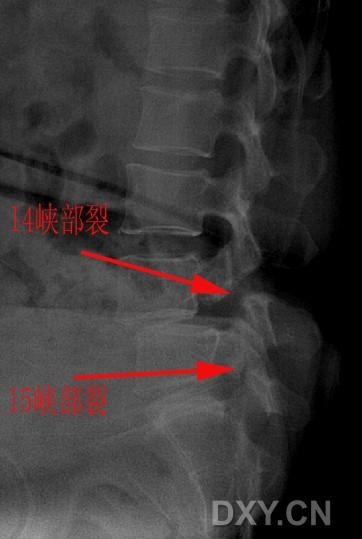

放射科放射科小马椎弓峡部裂

图片尺寸824x1128